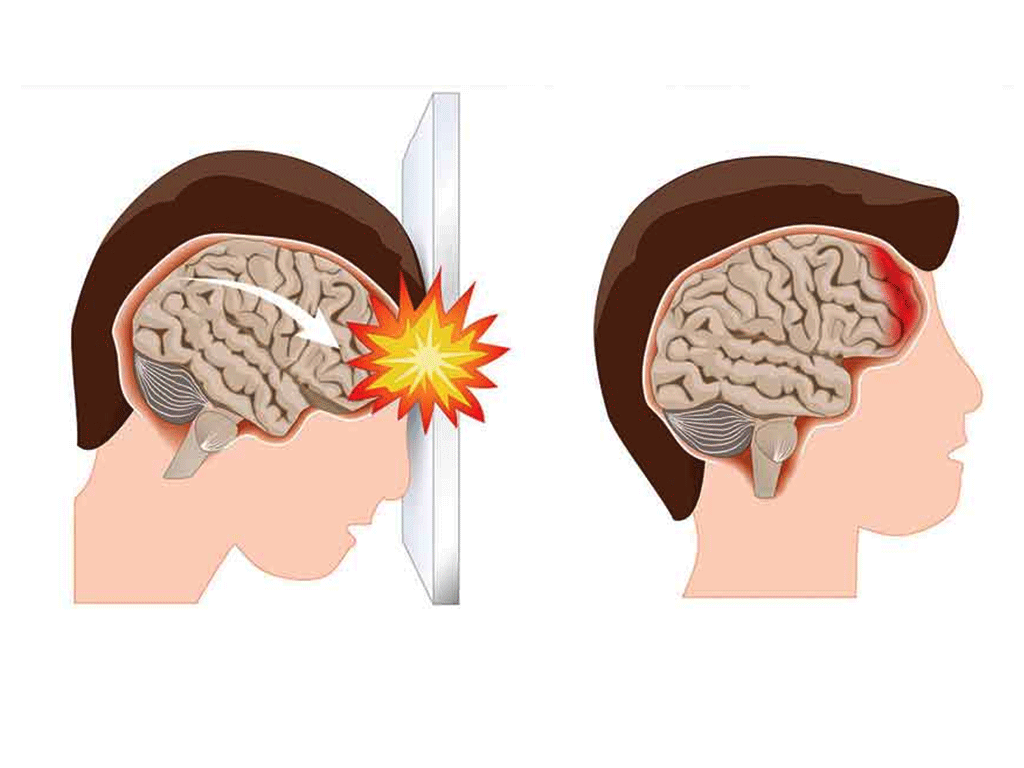

Concussion